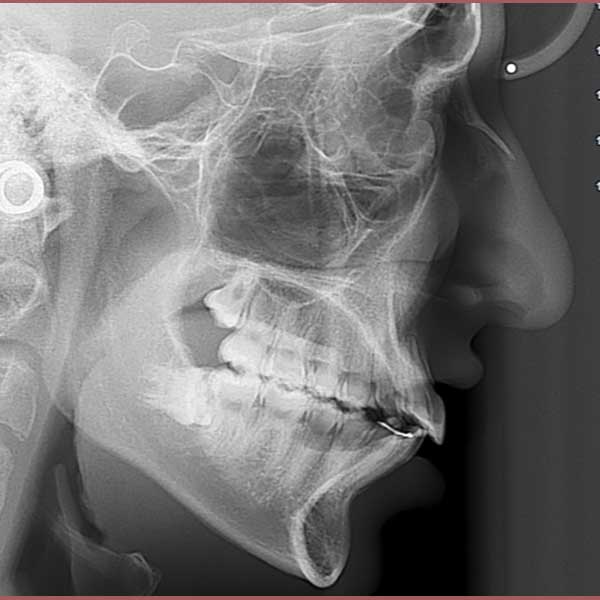

This little kid was suffering from severe protrusion (there was a space between the upper and lower front teeth), and regression in the lower jaw.

The condition was treated by fixed orthodontics and a functional device that serves to advance the lower teeth and the bearing bone forward and stimulate the advancement of the lower jaw forward and Put the upper teeth back.

The case was successfully treated without tooth extraction, as is usual in some similar cases.